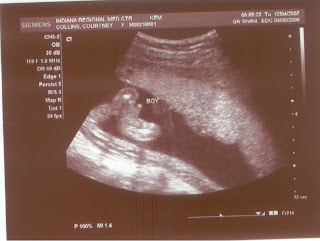

Baby Collins is a BOY! Nobody in the family was too surprised about that--we are just adding to the large number of Collins men! Zach and I are thrilled to know his gender, though, and to see him for the first time. Our ultrasound (my first) was a truly amazing experience. Our little one waved at us a few times and we saw his little mouth open and close. I'm not sure how long he is but he's measuring almost 20 weeks. (I'm almost 19 weeks along.) God truly works a miracle every time a baby is conceived!

As many of you know, we have been planning to name our boy Austin Zachary. Here are a few of Austin's first baby pictures!